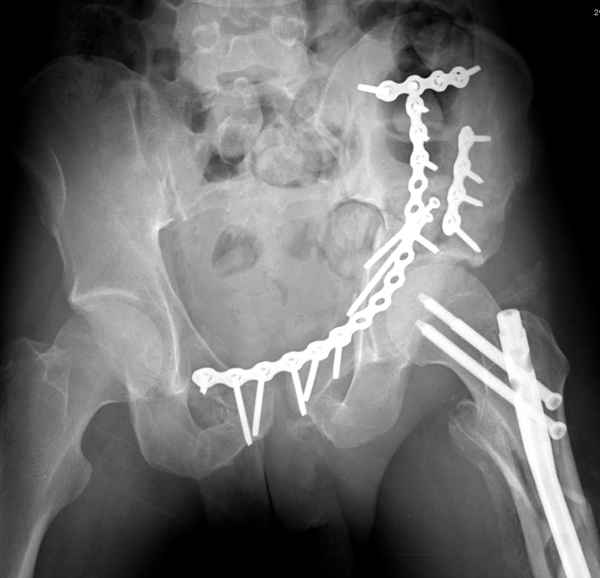

Здесь несколько вариантов двухколонных свежих переломов, которые были оперированы из одного-заднего, а также из двух: переднего и заднего доступов.